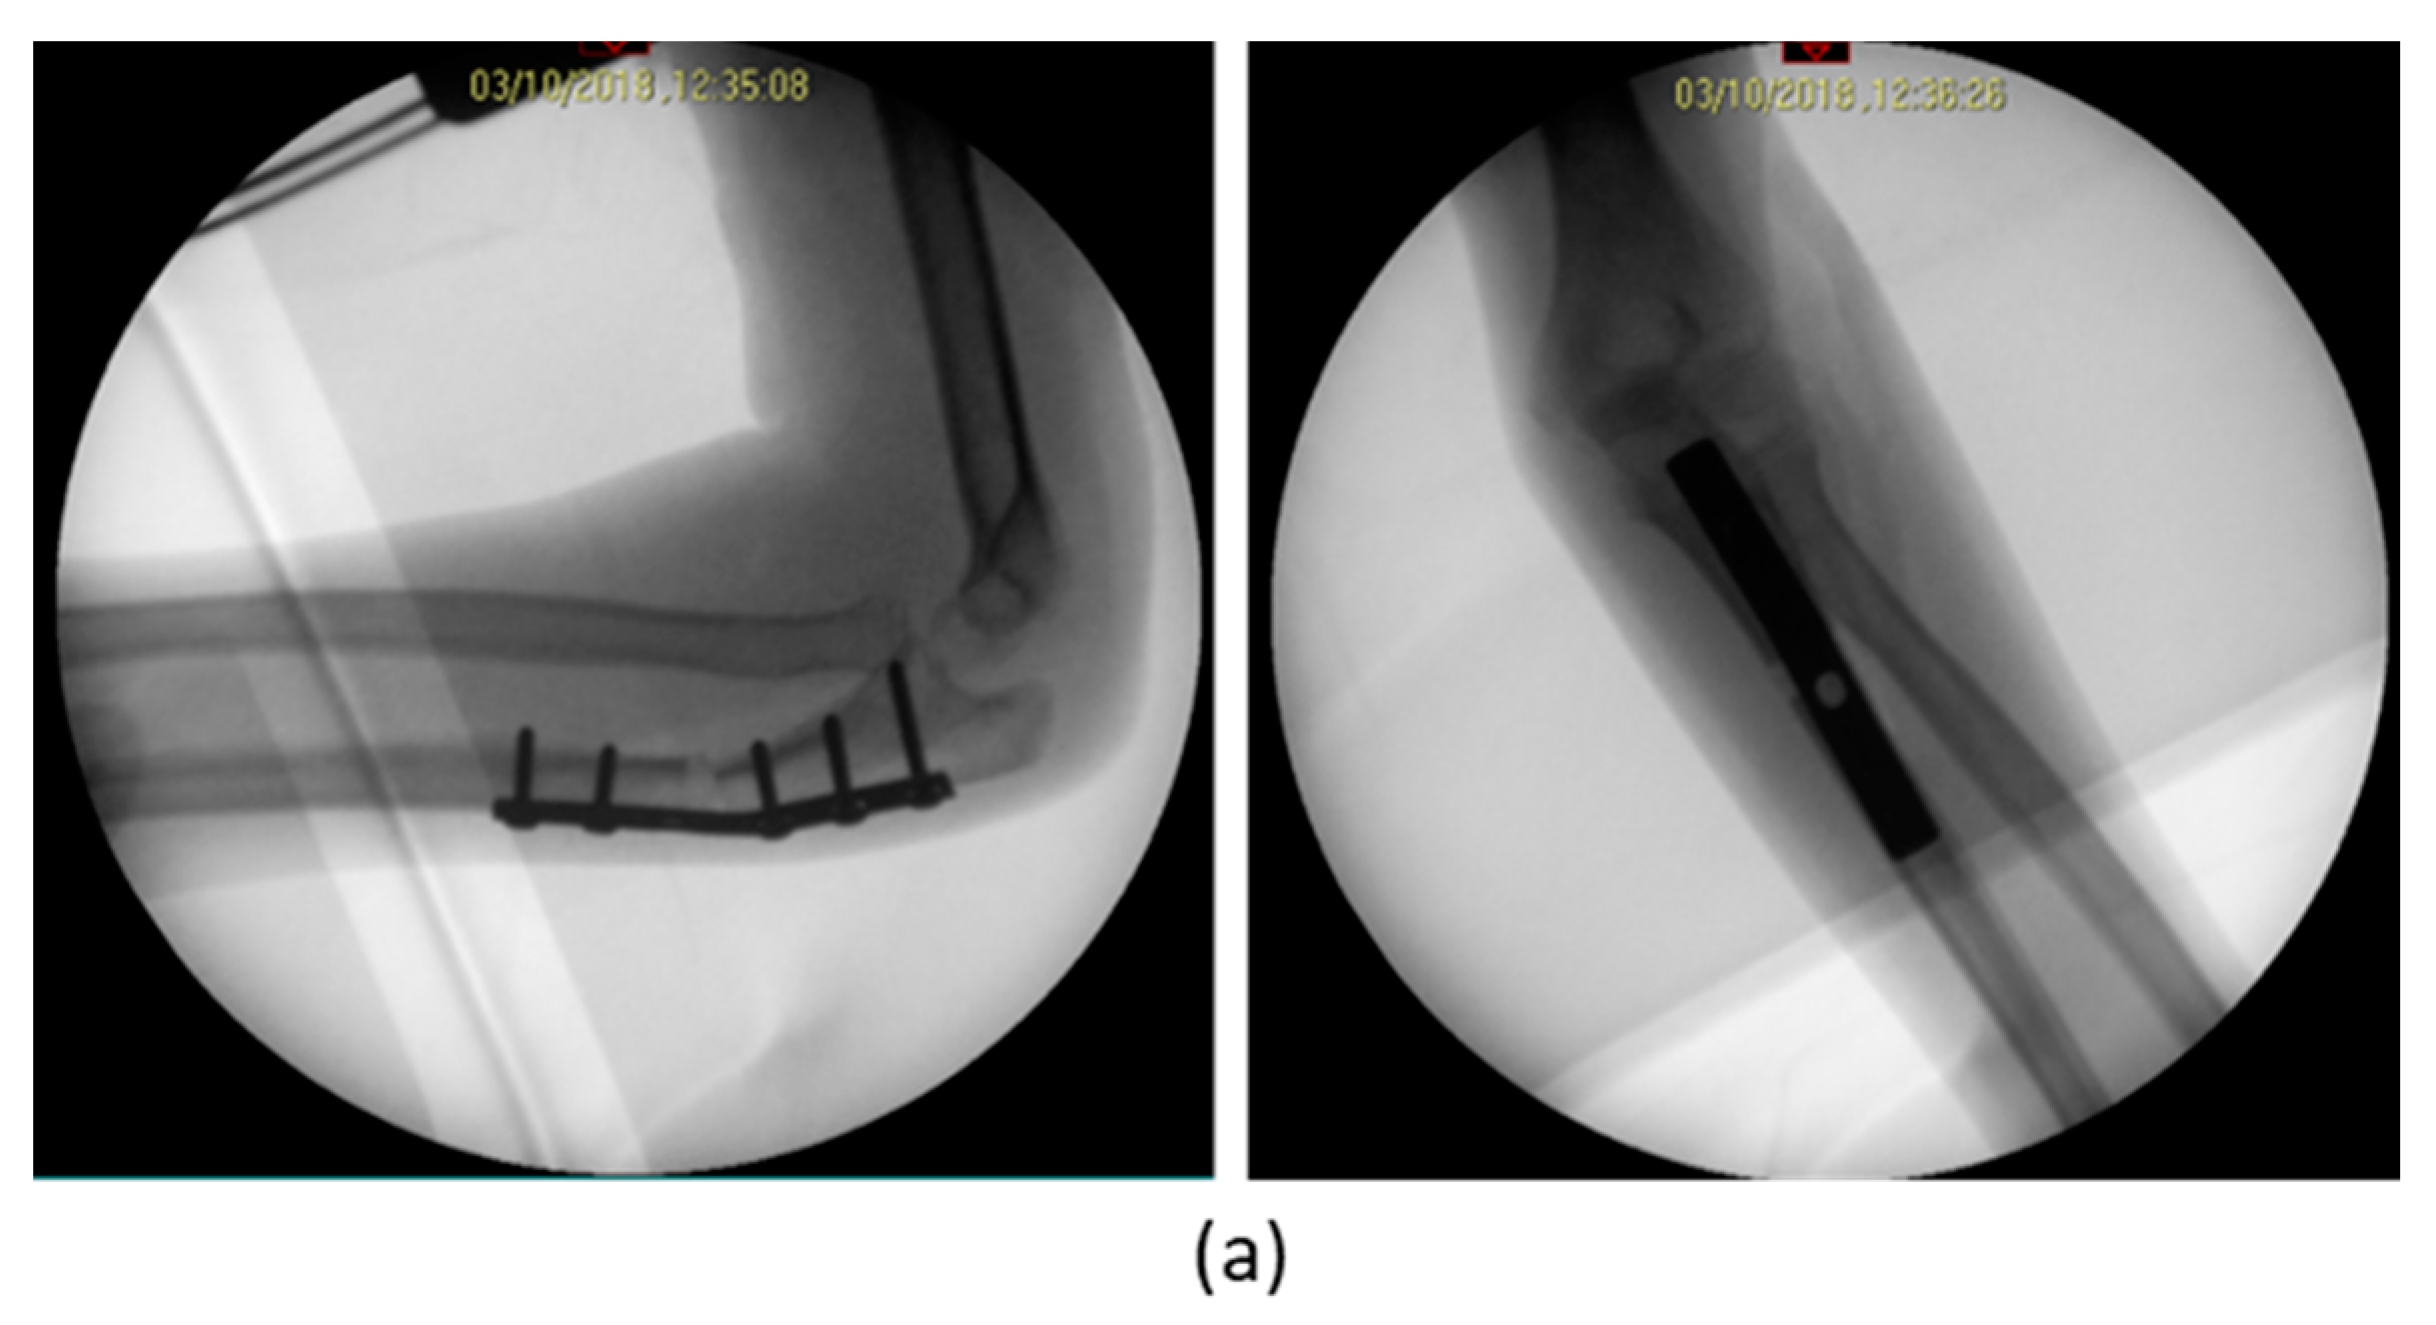

| 1 | F, 9 | Missed Monteggia Lesion | Post-traumatic | Proximal ulnar osteotomy stabilized with a 6-holes plate | None | Corrected |